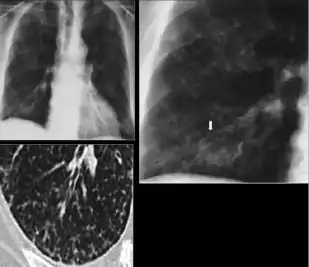

3. Discrete fibrotic scar with volume loss or retraction—Discrete linear densities with reduction in the space occupied by the upper lobe. Associated signs include upward deviation of the fissure or hilum on the corresponding side with asymmetry of the volumes of the two thoracic cavities.

Chest x-ray showing distinct fibrotic scar with volume loss or retraction with an upward deviation of the fissure or hilum on the corresponding side with asymmetry of the volumes of the two thoracic cavities.

5. Other—Any other finding suggestive of prior TB, such as upper lobe bronchiectasis. Bronchiectasis is bronchial dilation with bronchial wall thickening.

Chest x-ray showing course bronchiectasis of the lungs post-primary pulmonary tuberculosis.